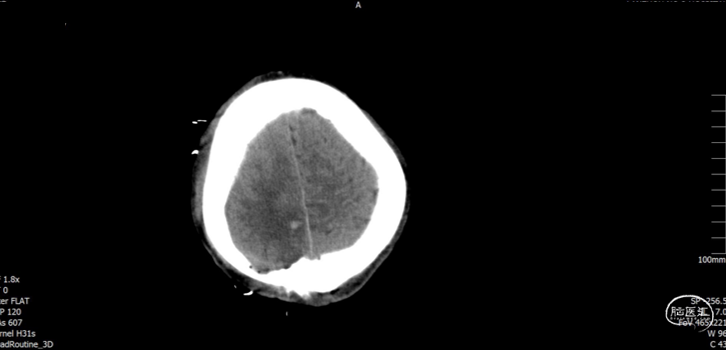

术后随访

术后CT